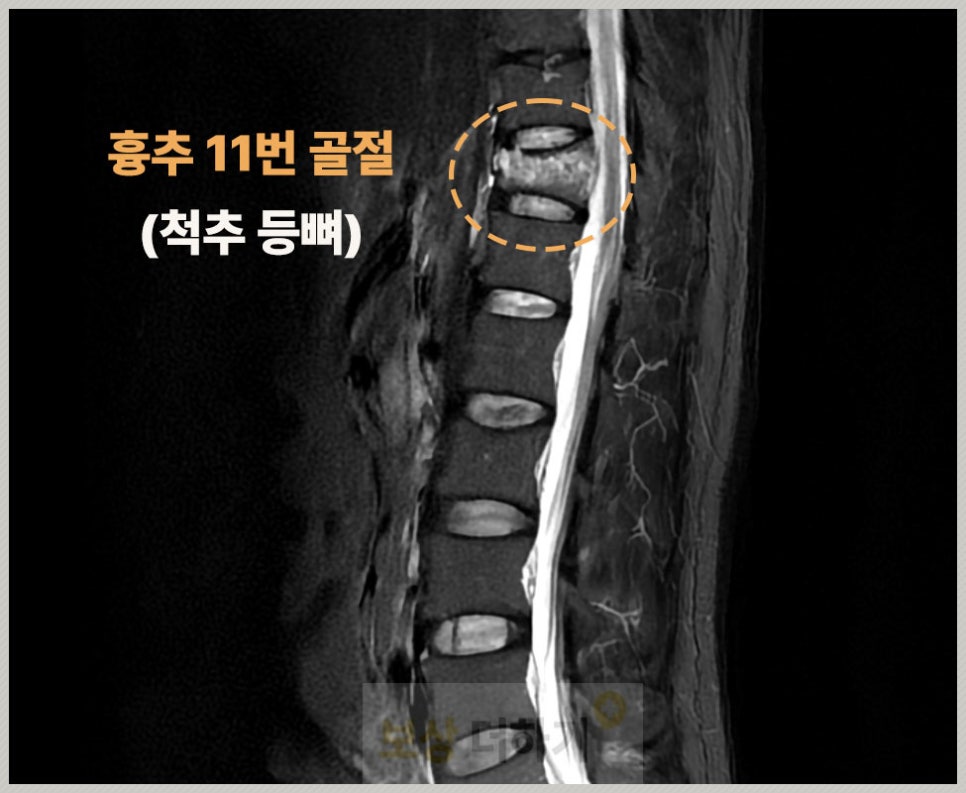

화장실에서 미끄러지면 엉덩방아를 찧는 경우가 정말 많습니다. 이때 충격이 [엉덩이 → 천골 → 요추 → 흉추 하부, 특히 11, 12번]으로 전달이 되죠. 따라서 이 부위에 골절이 일어나기 쉽습니다.

흉추 11번 ~ 12번은 등뼈인 흉추와 허리 뼈인 요추가 연결되는 부위 이 과도기 부위는 충격을 받을 때 힘이 집중되면서 골절이 잘 일어남

P 님 역시 이번 일로 흉추 11번 골절 진단을 받았습니다.